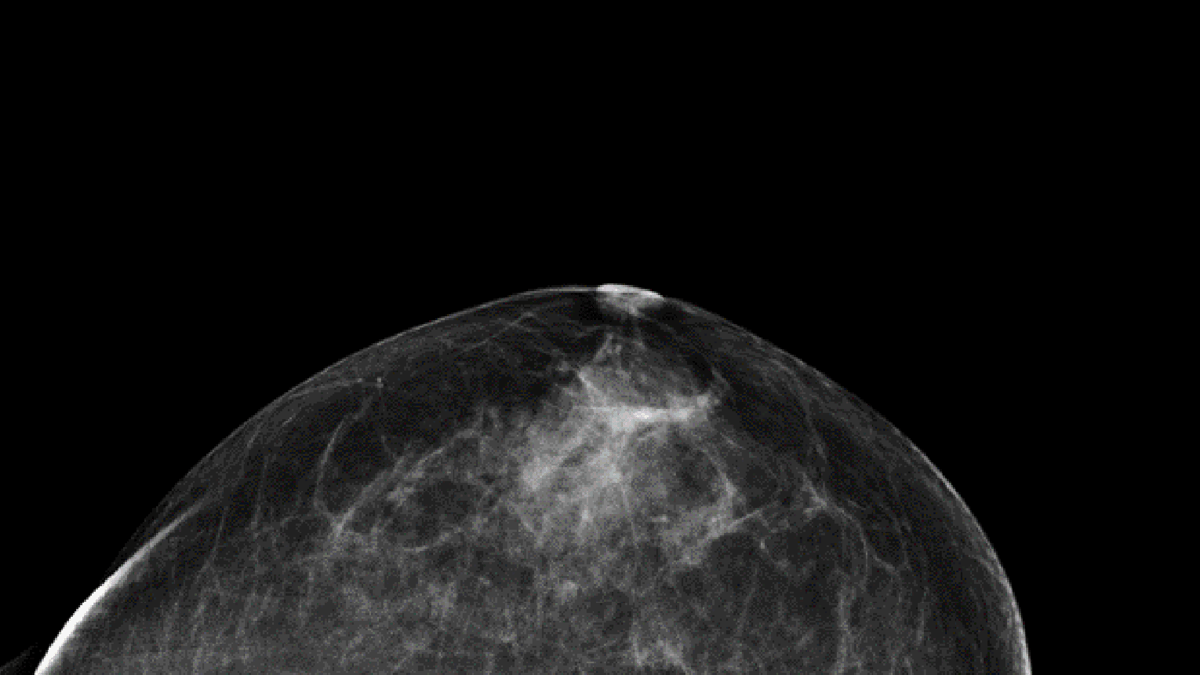

Enligt en utvärdering från Socialstyrelsen minskar mammografi dödligheten i cancer med 16 procent i åldersgruppen 40-49 år och drygt 20 procent i guppen 50–74 år. Röntgenbilden visar ett bröst utan cancer fotograferat uppifrån. De mörka partierna är fettvävnad och de vita kärl- och bindvävnad.